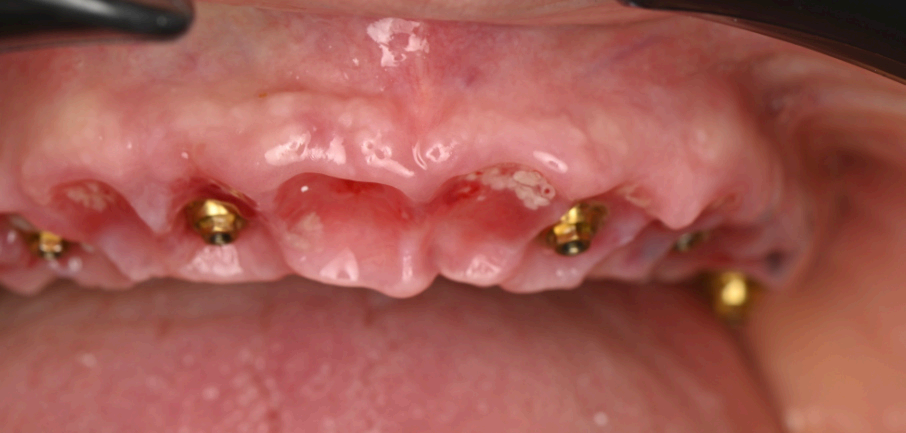

The surgical procedure was performed under local anesthesia in a single session. The residual roots at 13 and 21, along with the fractured teeth at 22 and 13, were extracted with minimal trauma to preserve the surrounding bone and soft tissue. The stackable guide was secured intraorally using the fxation bar anchored to the maxilla, providing a stable reference for implant placement (Fig. 2.2). Osteotomies were prepared at the planned sites (16, 14, 12, 22, 24, 26) using the guide’s drilling sleeves, ensuring accuracy in depth and angulation. Six implants were inserted, and multi-unit abutments (MUAs) were immediately placed to facilitate prosthetic connection (Fig. 2.3).

Following implant placement, intraoral photogrammetry was performed using the Shining3D Elite scanner. Scan markers were attached to the MUAs, and their positions were captured with high precision (Fig. 2.4, 3.4). Multiple scans were acquired, including the maxillary arch (Fig. 3.1), the fxation bar from the stackable guide (Fig. 3.2), the MUAs (Fig. 3.3), and the surrounding soft tissues (Fig. 3.5). The photogrammetry data was merged with conventional intraoral scans, using the fxation bar as a fduciary to align all datasets accurately (Fig. 3.7). A heat map generated in the software confrmed the precision of this alignment, with minimal discrepancies across the arch (Fig. 3.7). The scan markers were then converted to implant-specifc analogs compatible with the chosen implant system (Fig. 3.6).

Group 2: Surgical Procedure Fig. 2.1: 3D model of the stackable surgical guide with fxation bar. Fig. 2.2: Occlusal view of the osteotomy guide in use during surgery. Fig. 2.3: Frontal intraoral view post-implant placement with MUAs attached. Fig. 2.4: Occlusal view of coded scan body captured by Shining3D Elite photogrammetry.